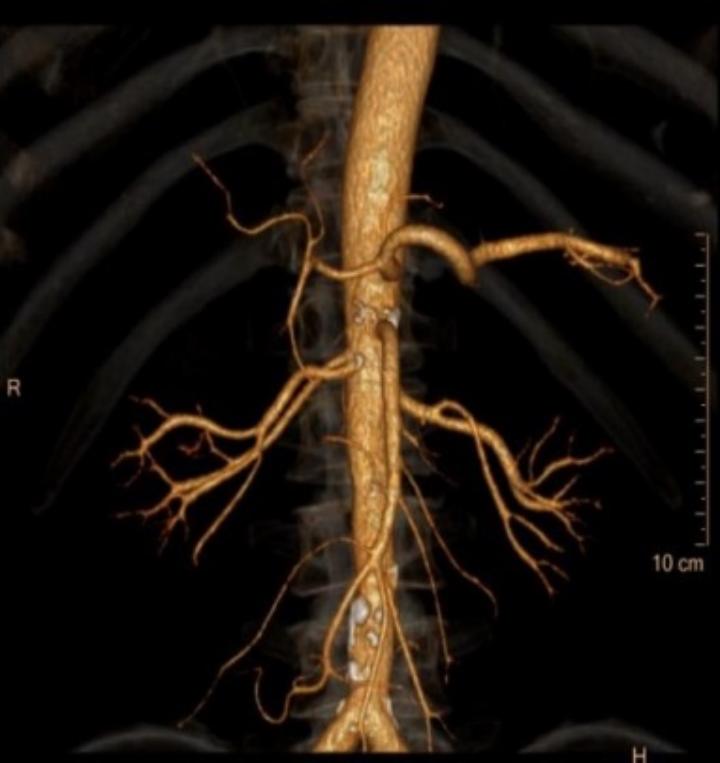

肾动脉CTA:右肾占位,大小约4.7*4.5cm,类圆形低密度影,增强扫描呈不均匀强化,考虑恶性;右肾动脉分支供血。

1.游离动脉:结合术前影像资料,有2支右肾动脉直接从腹主动脉发出,都是肾脏的主要血管,越过腔静脉后走形于右肾静脉偏下方的位置,因此我们在右肾静脉下方寻找到两支右肾动脉并分别予以游离标记。